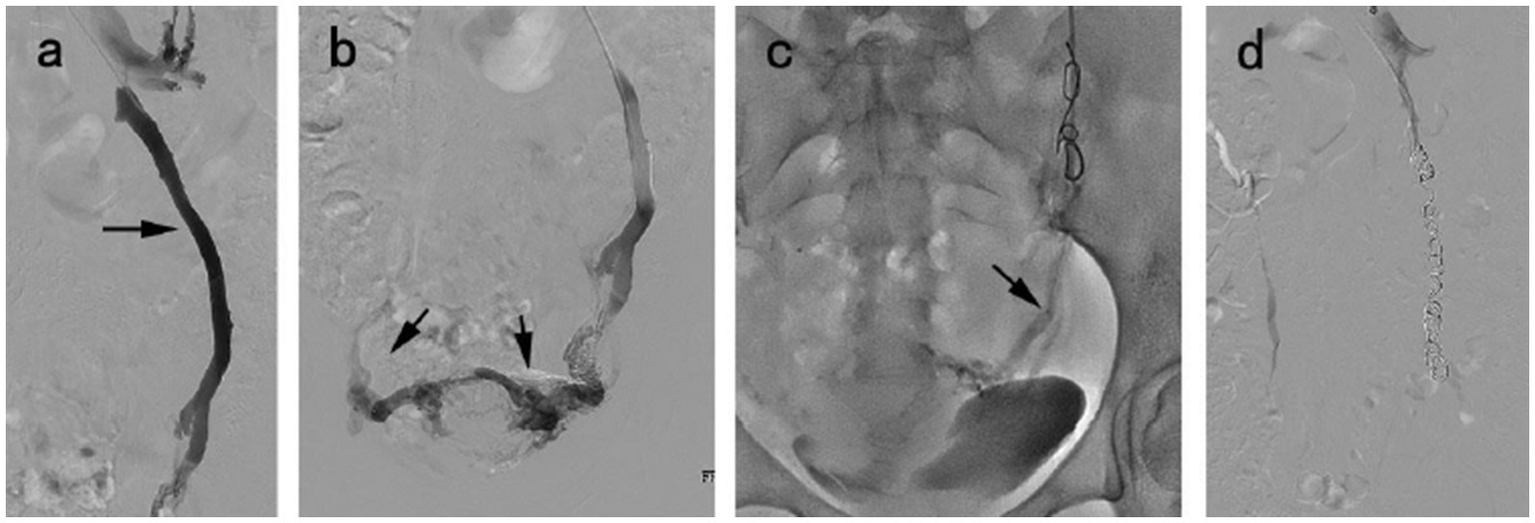

Figure 2

A 38 year-old woman diagnosed with VO-CPP and symptoms duration of 2 years. (a) Venography of the left ovarian vein showed venous distension, reflux (black arrow). (b) Congestion of the pelvic venous plexus. (c) The microcatheter (black arrow) was inserted into pelvic venous plexus via the previously placed coil to inject 3% polidocanol foam. (d) The disappearance of venous reflux following embolization.